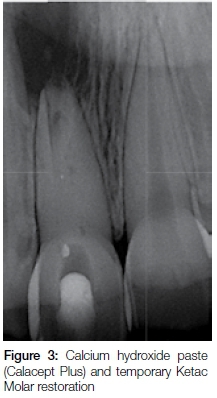

The root canal was chemically disinfected with 3.5 % sodium hypochlorite, excess fluids from the root canal were removed with paper points and an intra-canal medicament of calcium hydroxide paste was placed (Calasept Plus, Nordiska Dental, Sweden) (Figure 3).

The tooth was sealed with Ketac Molar (3M ESPE) as a temporary restoration and post-operative instructions were provided. The patient was scheduled for his next appointment four weeks later.